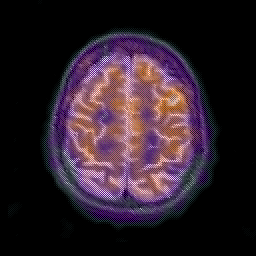

Alzheimer's disease: overlay -- Slice #20

[Home][Help][Clinical] Slice 20